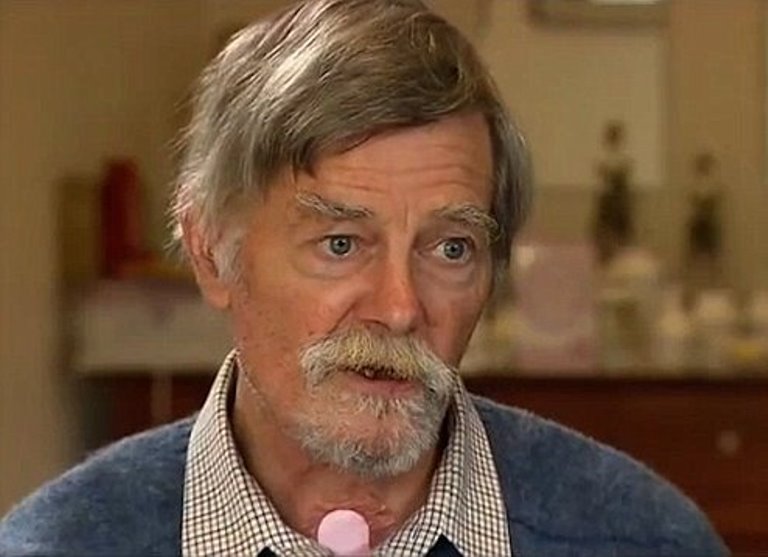

68-year-old Bill Singleton was forced to drive himself almost 33 kilometers to a hospital after accidentally cutting his face with a chainsaw.

The Australian grandfather told his wife, Lynette, he was only going to cut some firewood and would return home soon.

Bill had two more operations to secure his jawline and to prepare his gums for a new set of teeth. He said that the worst thing about it is that it has changed his diet.

“He’s just dying for a steak,” Lynette said.